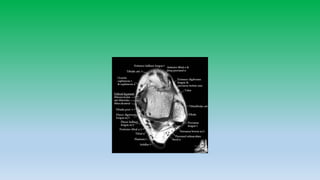

Anterior ankle tendons:

• There are four tendons from medial to lateral –TA, EHL,EDL,PT. These

tendons serves as dorsiflexors of foot and ankle.

Medial ankle tendons:

• Tibialis posterior attaches to navicular , cuniform and base of 1st-4rt

metatarsal. Tibialis posterior tendon provides support to longitudinal

arch of foot and injury can cause flat foot.

• Flexor digitorum longus passes lateral to tibialis posterior tendon and

inserts to distal phalanges of 2nd-5th toes.

• Flexor halluces longus passes beneath sustentaculum talus and insert

into base off 1st toe distal phalanx. Sheath of FHL tendon

communicates with ankle joint and fluid within sheath is common.

Medial aspect

Tendon: Tibialis posterior

Flexor digitorum longus

Flexor H. longus

Ligaments: Deltoid ligament